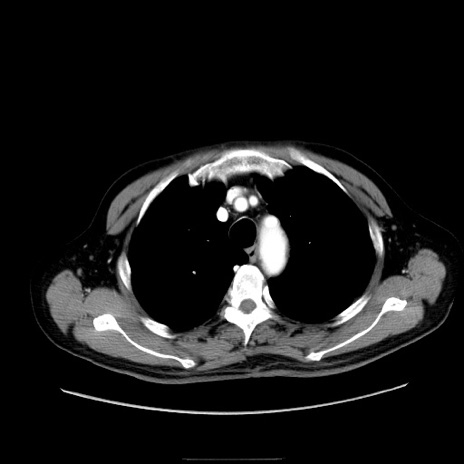

症例30(横断像)

【症例】80歳代男性

【主訴】臍周囲痛

【現病歴】約6時間前から臍下部痛が出現。次第に腹部膨隆・背部痛も生じてきたため来院。背部痛の場所は変化しない。

【身体所見】意識清明、BT 36.3℃、BP  131/87mmHg、P 87bpm、SpO2 100%(RA)、臍周囲自発痛・圧痛あり、反跳痛なし、自発痛部位に一致して板状硬あり、腹部膨隆、腸雑音減弱、CVA tenderness両側陰性。